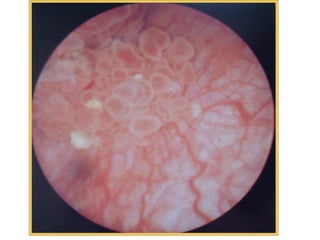

• Superficial bladder tumor: Ta&T1 and CIS,

usually recur in other site of the bladder(70%),

but rarely invades bladder wall (10%), solitary or

multiple with mobile fronds long stalk and narrow

base. CIS carcinoma in situ: high grade

intraepithelial carcinoma, appear as velvety

hyperemic areas.

Gross Types

• Papillary: sea-weed appearance

• Cauliflower mass with stunt fronds, some

necrotic.

• Nodular

• Ulcerative.